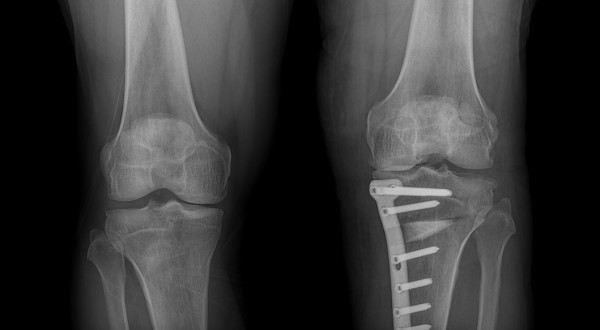

#절골수술(Osteotomy)의 이해

절골수술은 무릎 관절의 비정상적인 정렬을 교정하기 위한 수술적 방법입니다. 이 수술은 주로 관절염으로 인한 통증과 기능 장애를 겪고 있는 환자들에게 시행됩니다. 수술 과정에서는 뼈를 절단하고 재정렬하여 무릎에 가해지는 압력을 분산시킴으로써, 관절에 대한 스트레스를 줄이고 통증을 완화시킵니다. 이러한 접근법은 관절의 수명을 연장시키고, 궁극적으로는 관절 교체 수술을 피할 수 있게 해줍니다.